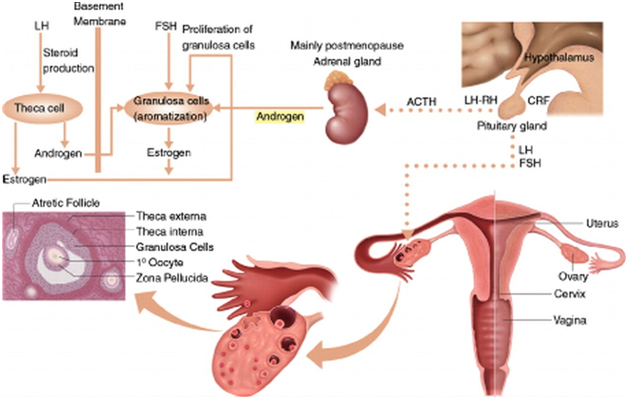

- The Ovaries (Figures 1&2)

- The ovaries, under the control of luteinizing hormone (LH), produce 50% of the total testosterone that rises to 75% at midcycle.

- The ovaries also secrete 50% of the total androstenedione and small amounts (20%) of DHEA.

- Testosterone is used as a marker of ovarian androgen secretion; however, the adrenals, via peripheral conversion of androstenedione to testosterone, also contribute to total testosterone.

- The Adrenals

- The adrenal glands produce all the DHEAS and 80% of the DHEA.

- The adrenals also secrete 50% of androstenedione and 25% of the circulating levels of testosterone.

- DHEAS and 11-androstenedione are not secreted by the ovaries and, therefore, are used as markers of adrenal androgen secretion.

- Their secretion depends on (ACTH); prolactin and estrogen can affect adrenal androgen production…

Figure 1 Synthesis of sex steroids, in women, androgens and their precursors are produced by both the adrenal glands and the ovaries in response to their respective ACTH and luteinizing hormone (LH). In the ovaries, androgens are produced as precursors in the synthesis of estrogen and estradiol. The theca cells of preantral (secondary) ovarian follicles produce and rostenedione and testosterone in response to luteinizing hormone. (Courtesy of; Functioning Ovarian Tumors: Direct and Indirect Findings at MR Imaging: Yumiko O. Tanaka et al.)